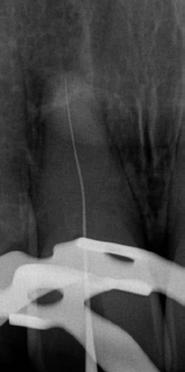

Az átöblítés során a roots magazin egy korábbi számában (2/2022) bemutatott protokollt alkalmaztam (Less-Prep Endo enhanced irrigation protocol). Az átöblítőszer aktiválása SkyPulse lézer (Fotona) segítségével AutoSWEEPS (shock wave enhanced emission photo-acoustic streaming) módban történt. Ennek köszönhetően az MB2 csatorna középső harmada is átjárhatóvá vált a C-PILOT tűk számára. Ezt radio-

lógiai felvételek segítségével is igazoltuk (6–7. ábra). Az MB1 és MB2 csatornák között az átöblítőszerek szabad áramlását észleltük. A gyökércsatornákat crown-down technika szerint a C-PILOT és Perfect Shape gépi gyökérkezelő tűkkel megmunkáltuk, de időhiány miatt a megmunkálás teljes munkahossznál rövidebb mélységben történt. Az ülés végén a fogat kompozitból készült ideiglenes tömés segítségével zártuk és a pácienst egy másik időpontra visszarendeltük.